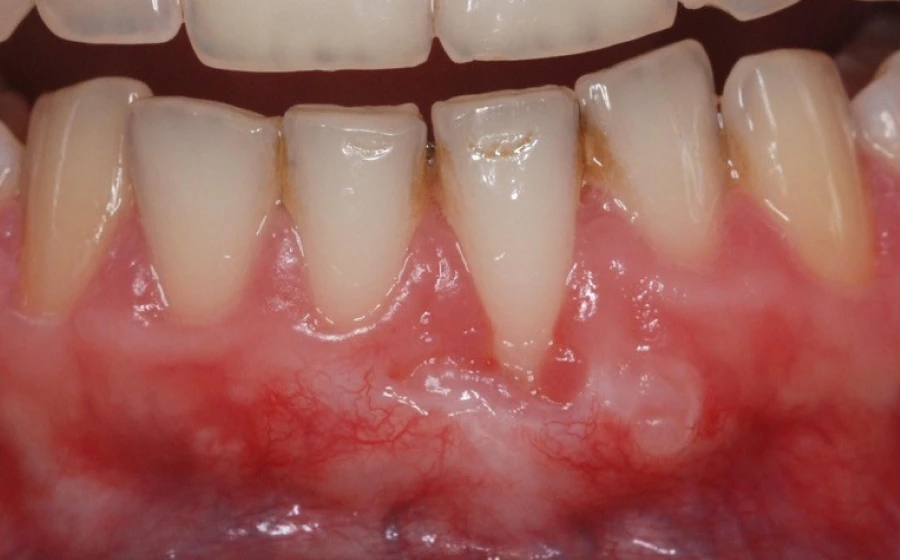

La récession gingivale

La récession gingivale est l’une des principales indications. Elle survient lorsque les gencives se rétractent, exposant les racines des dents. Cela peut être dû à un brossage agressif, à une maladie parodontale ou à un traumatisme. La chirurgie muco-gingivale couvre les racines exposées et renforce les gencives.

L’insuffisance de tissu kératinisé

Une autre indication est l’insuffisance de tissu kératinisé autour des dents mais aussi des implants dentaires. Le tissu kératinisé est essentiel pour la stabilité des gencives, une insuffisance de ce tissu peut entraîner des infections et des inflammations. La chirurgie muco-gingivale ajoute du tissu kératinisé pour améliorer la santé des gencives.